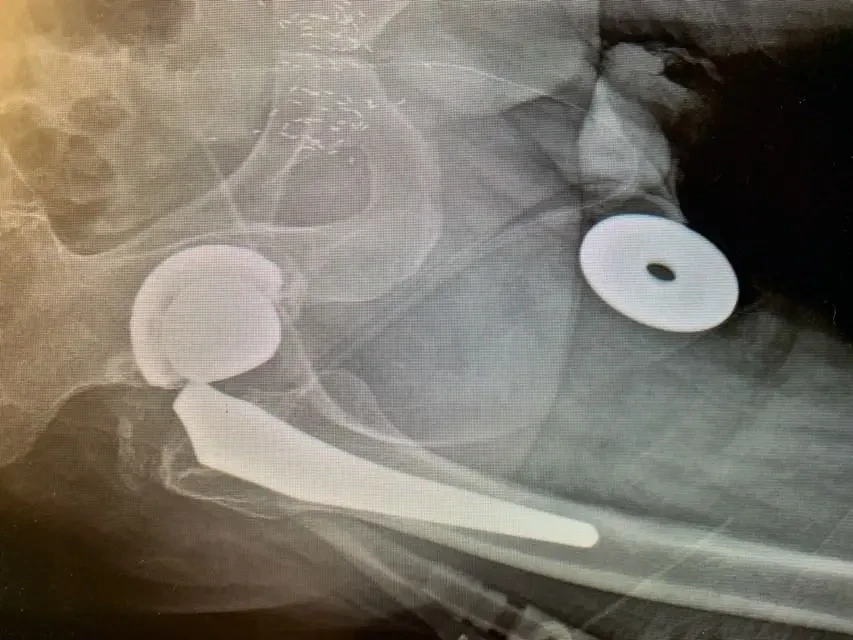

Utilizamos el mismo abordaje quirúrgico que el cirujano anterior, en este caso el abordaje lateral, y expusimos la articulación de la cadera de forma cuidadosa y meticulosa. Una vez completada esta operación, dislocamos la cadera y recuperamos el componente de la cabeza femoral, lo que reveló que el cuello del componente femoral había estado pistoneando dentro del componente de la cabeza, lo que había provocado que se erosionara hasta parecerse a la punta de un lápiz.

Retiramos con cuidado el componente femoral y el revestimiento de plástico del componente acetabular; las pruebas de la carcasa metálica revelaron que era estable, por lo que se decidió que esta parte de la intervención original permanecería intacta. Preparamos e insertamos el componente femoral de revisión sin eventos y probamos componentes de cabeza femoral con componentes de revestimiento acetabular de prueba para asegurarnos de que la cadera permanecía estable. Una vez que estuvimos satisfechos con los tamaños de nuestros componentes, se colocaron los componentes definitivos y se completó el procedimiento.